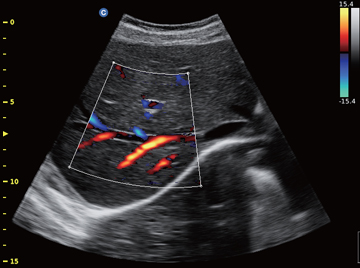

ECO 6

Portabilan pristupačan kolor dopler

Polja primene:

Radiologija

Akušerstvo i ginekologija

POC

Veterina